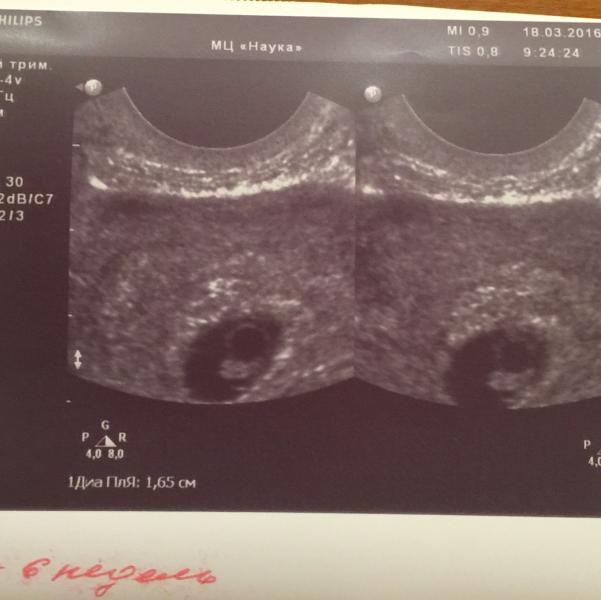

Огромное всем спасибо за поздравления!!! 😘😘😘 Я всю ночь не спала, так как для нас это был спорный момент. Мне ставили непроходимость, поэтому боялась внематочной, но всё обошлось! Ура!!! 🎉🎉🎉

В интернете есть тест по первому фото узи) у нас сошлось)